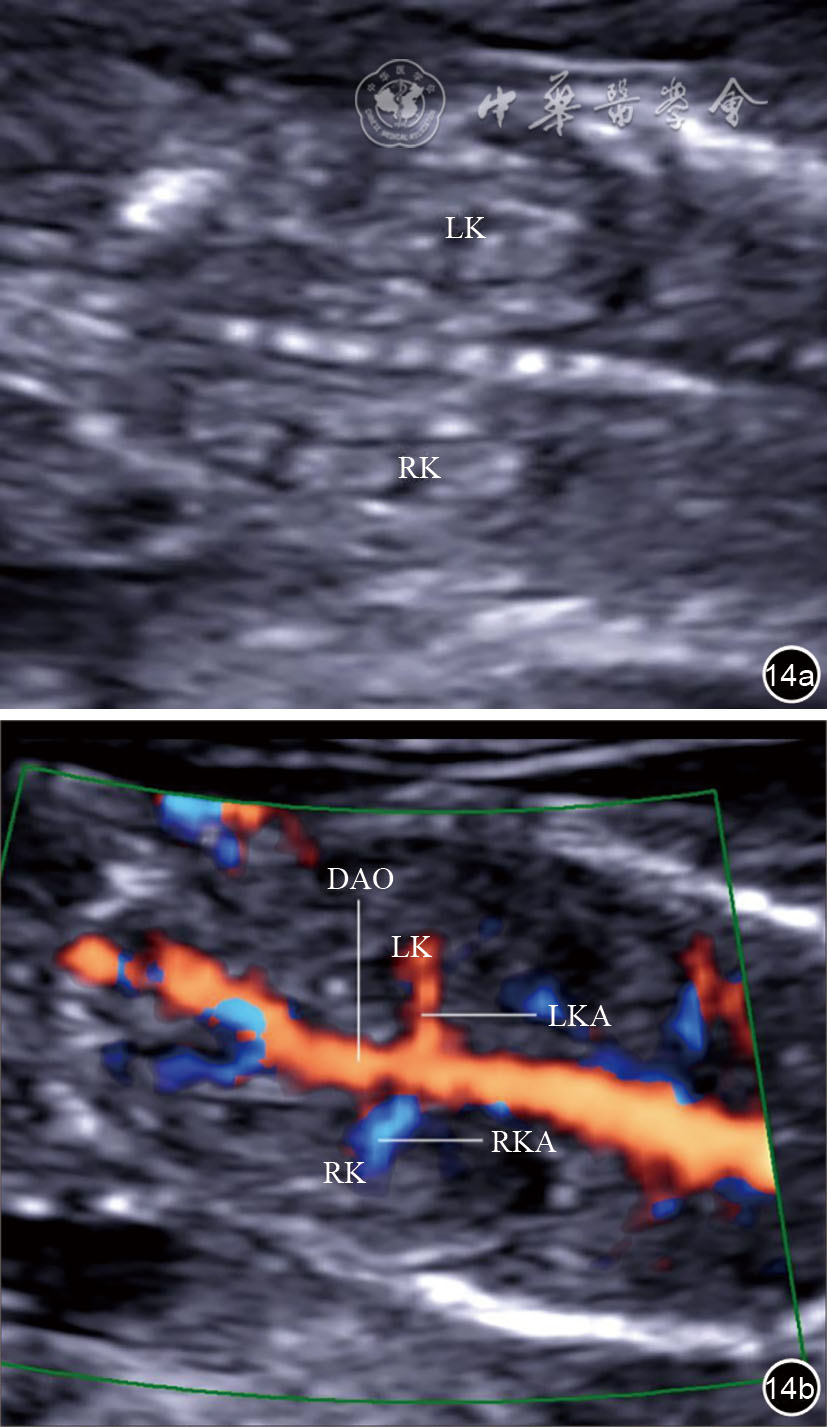

图14 双肾冠状切面超声图像。图a为妊娠13周胎儿双肾冠状切面二维声像图;图b为妊娠13周胎儿双肾冠状切面彩色多普勒血流声像图 注:LK为左肾;RK为右肾;LKA为左肾动脉;RKA为右肾动脉;DAO为降主动脉